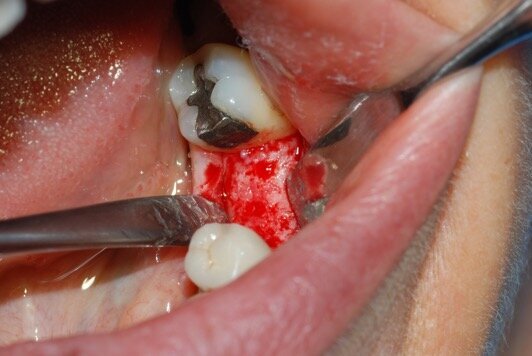

Dopo l’anestesia locale, è stato scollato un lembo a spessore totale e il dente estratto in modo atraumatico (Fig. 1). Successivamente, l’alveolo post-estrattivo è stato zeppato con granuli di osso bovino decellularizzato (Re-Bone®, Ubgen, Padova/Italy) e utilizzata una membrana di pericardio bovino come barriera (Shelter® Membrane, Ubgen, Padova/Italy) (Fig. 2).